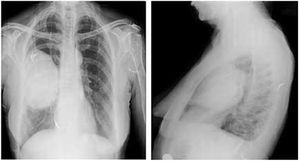

Case History: Patient presented for follow up after completion of chemotherapy and radiotherapy for hypopharyngeal cancer.

Published: May 12th 2015 | Updated: